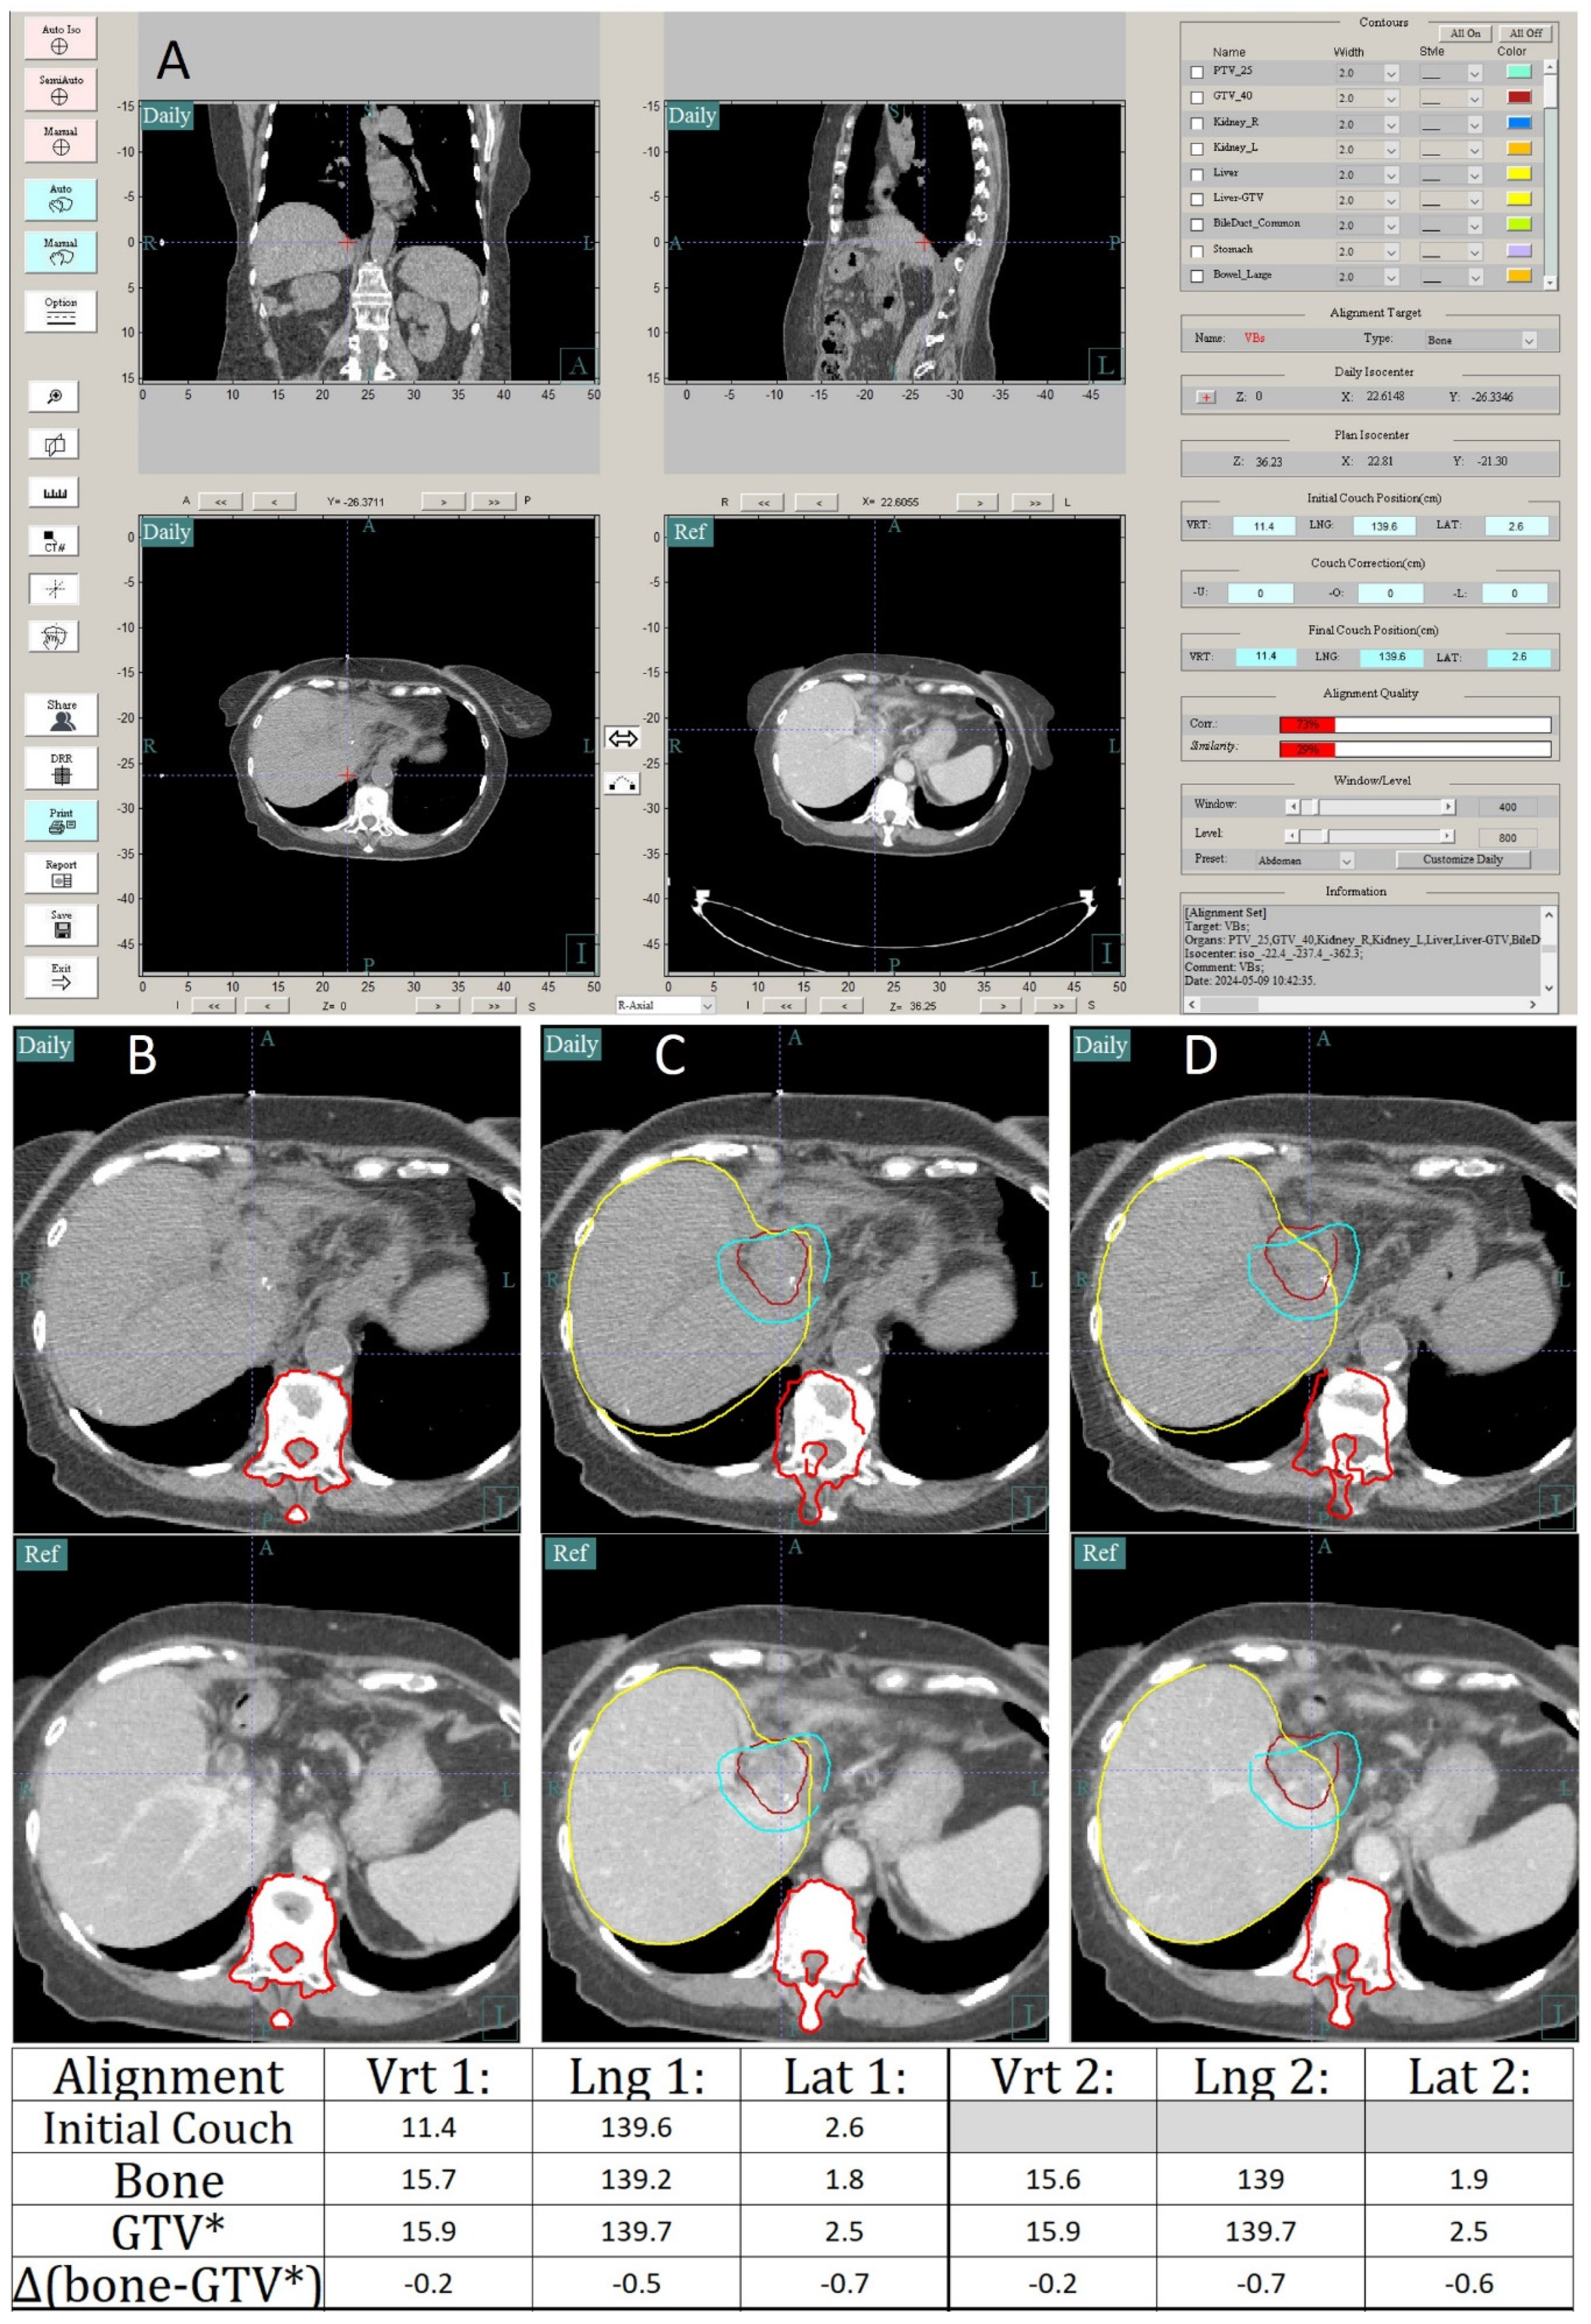

3.1. Case Study 1